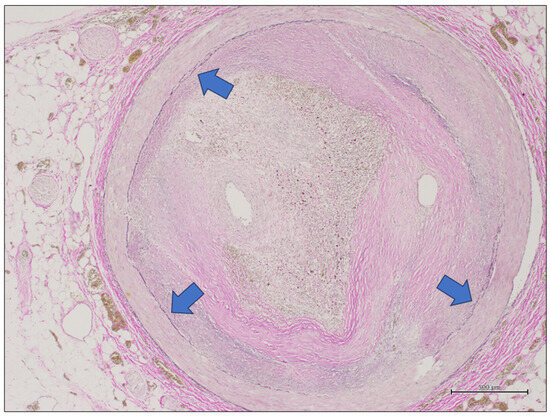

2.2. Coronary Artery Gross Evaluation and Sampling, Histology, and Ancillary Technique

2.3. Digital Pathology

2.4. Pathologist Evaluation